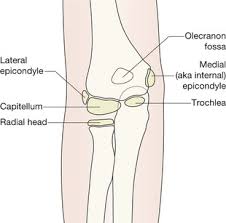

A patient's guide to elbow anatomy. Normal radiographic anatomy of the elbow | radiology case human anatomy and physiology. To install xray anatomy on your windows pc or mac computer, you will need to download and install the windows pc app for free from this post.

There is a printable worksheet available for download here so you can take the quiz with. Radiology imaging anatomy for radiology student and tech / technologist ( xray ct mri ). It contains information about the normal anatomy and the most common pathology. Documents similar to common errors in xray interpretation 2.